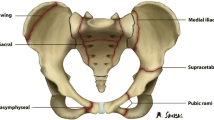

Stress injuries represent a spectrum of osseous abnormalities that occur in response to chronic repetitive stress applied to healthy bone. Stress injuries are common in athletes and represent approximately 10% of all injuries seen in sports medicine clinics. Running is the activity most commonly associated with these injuries. The vast majority of stress injuries involve the tibia followed in order of decreasing frequency by the tarsal bones, metatarsals, femur, and fibula [1].

Radiographs are commonly used to evaluate patients with suspected tibial stress injuries. Radiographic manifestations of stress injuries include decreased cortical density, periosteal reaction, endosteal thickening, and a cortical fracture line [2–5]. However, radiographs are insensitive for detecting early tibial stress injuries and are initially negative in the vast majority of symptomatic patients [6–9]. For this reason, most patients with clinical signs and symptoms of tibial stress injuries who have normal radiographs are further evaluated with more sensitive imaging modalities.

Stress injuries of the tibia occur when bone does not adapt normally to repetitive stress [22]. Stress related to daily activity stimulates bone to strengthen and remodel its architecture to better withstand its mechanical environment. Normal stress stimulates osteoclastic activity that creates resorption cavities within the tibial cortex that eventually fill in with lamellar bone over the course of several months [23, 24]. Chronic repetitive stress to the tibia may result in an imbalance between osteoclastic and osteoblastic activity, which ultimately weakens bone [22]. If the repetitive stress continues, repair mechanisms may be overwhelmed and a true fracture may develop through the weakened bone [2, 22, 25]. However, most tibial stress injuries represent stress reaction and not stress fracture and show no evidence of a break in the continuity of bone on histologic analysis [26, 27]. In most cases, the chronic repetitive stress on the tibia is discontinued prior to the development of a true fracture [2, 22, 25].

Radiographs have long been used to evaluate patients with tibial stress injuries. Radiographic manifestations of tibial stress injuries include decreased cortical density, periosteal reaction, endosteal thickening, and a cortical fracture line. Decreased cortical density has been described as the earliest radiographic finding of stress injury and is thought to represent hyperemia and edema of the injured tibial cortex [4]. Periosteal or endosteal proliferation may later form at the site of repetitive stress in an attempt to buttress the weakened cortical bone. If the chronic repetitive stress continues, a true fracture through the tibial cortex may eventually occur [2].